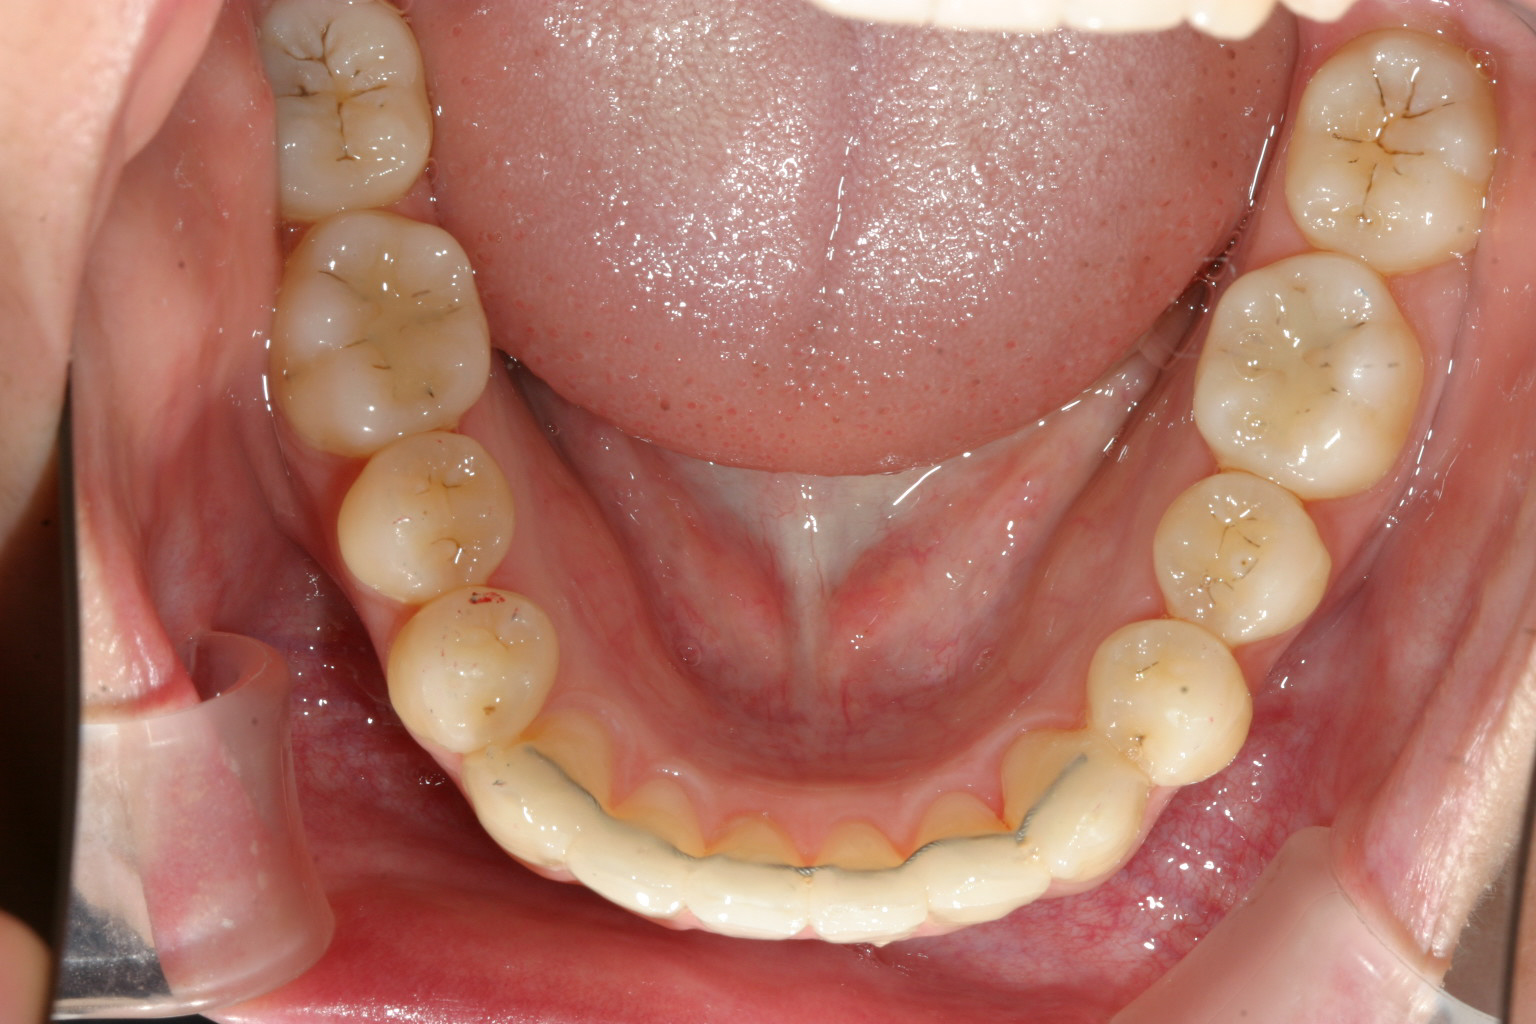

下顎もU字に変えて配列しています。